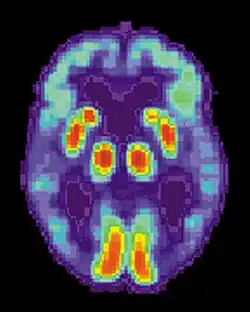

| Diagram of a normal brain compared to the brain of a person with Alzheimer's | |

AD is usually clinically diagnosed based on a person's medical history, observations from friends or relatives, and behavioral changes. The presence of characteristic neuropsychological changes with impairments in at least two cognitive domains that are severe enough to affect a person's functional abilities are required for the diagnosis. Domains that may be impaired include memory (most commonly impaired), language, executive function, visuospatial functioning, or other areas of cognition. The neurocognitive changes must be a decline from a prior level of function and the diagnosis requires ruling out other common causes of neurocognitive decline.[127][128][129] Advanced medical imaging with computed tomography (CT) or magnetic resonance imaging (MRI), and with single-photon emission computed tomography (SPECT) or positron emission tomography (PET), can be used to help exclude other cerebral pathology or subtypes of dementia.[130] On MRI or CT, Alzheimer's disease usually shows a generalised or focal cortical atrophy, which may be asymmetric. Atrophy of the hippocampus is also commonly seen. Brain imaging commonly also shows cerebrovascular disease, most commonly previous strokes (small or large territory strokes), and this is thought to be a contributing cause of many cases of dementia (up to 46% cases of dementia also have cerebrovascular disease on imaging).[127] FDG-PET scan is not required for the diagnosis but it is sometimes used when standard testing is unclear. FDG-PET shows a bilateral, asymmetric, temporal and parietal reduced activity.[127] Advanced imaging may predict conversion from prodromal stages (mild cognitive impairment) to Alzheimer's disease.[131] FDA-approved radiopharmaceutical diagnostic agents used in PET for Alzheimer's disease are florbetapir (2012), flutemetamol (2013), florbetaben (2014), and flortaucipir (2020).[132] Because many insurance companies in the United States do not cover this procedure, its use in clinical practice is largely limited to clinical trials as of 2018.[133]